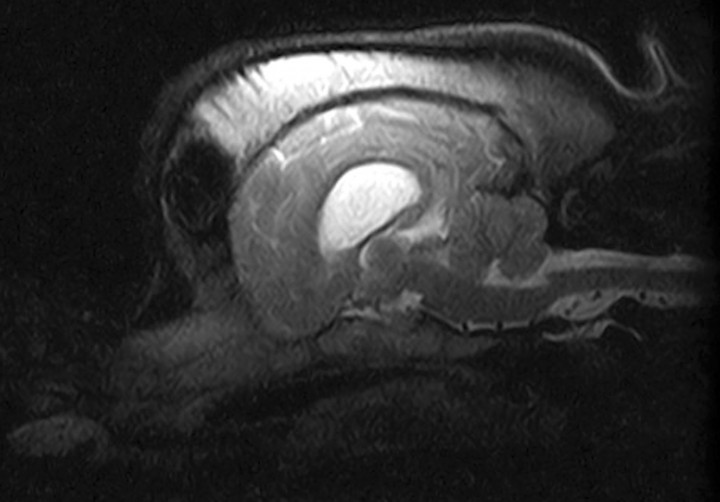

Transcurridos 6 meses se realizó una segunda TC en la que la lesión ósea se mantenía en dimensiones similares, pero con una disminución considerable de la atenuación ósea en comparación con la primera (Fig. 2B). Esta vez se procedió a realizar también una resonancia magnética (RM) para comprobar que la lesión no afectase a otras estructuras (Fig. 3). Se observó una dismorfia del hueso frontal derecho que deformaba el cráneo en ese lado, sin que existiera un crecimiento óseo hacia el interior de la cavidad craneal. El seno frontal derecho presentaba mayor tamaño, pero estaba normalmente neumatizado. No se observaron alteraciones en los demás huesos que configuran la bóveda craneal ni la base del cráneo. Respecto al parénquima cerebral, cerebeloso y tronco cerebral, no se observaron alteraciones estructurales ni de la señal valorables en las distintas secuencias realizadas.

<p>Imagen de Resonancia Magnética, plano sagital en T2. No se observan lesiones en estructuras adyacentes.</p>

Imagen de Resonancia Magnética, plano sagital en T2. No se observan lesiones en estructuras adyacentes.